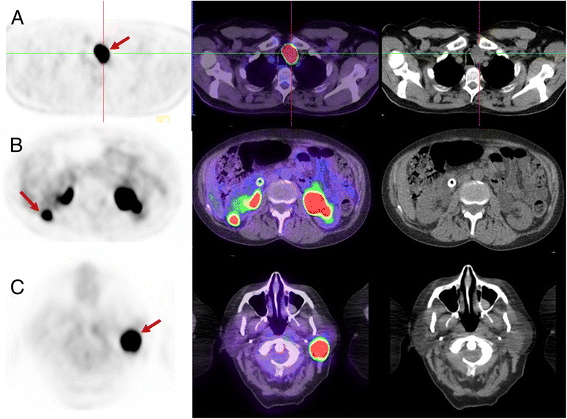

Next, we review the coronal PET images and triangulate apparent abnormalities on other planes and the MIP image. It is important to review these images on a workstation that has capacity to triangulate findings in axial, coronal and sagittal planes. We find the coronal images particularly helpful for detecting small abnormalities, particularly within the lungs and subcutaneous tissue. Any lesions identified on the PET are then correlated with the CT images, reviewing soft tissue, lung and bone windows as appropriate to the location of the abnormality. We selectively review the non-attenuation corrected (NAC) series when there is uncertainty about possible reconstruction artefacts due to metallic objects or patient movement between PET and CT components. Finally, it is important to widen the PET window in order to review the brain, otherwise easily discernible abnormalities can be missed (see Fig. 4).

Patient with diffuse large B cell lymphoma. On the standard windowing, no abnormality is readily identified in the brain (a coronal & axial slice, b MIP image). By increasing the upper SUV threshold, abnormal uptake becomes readily becomes visible (c MIP image, d coronal & axial slice). This corresponded to a MRI abnormality which was not reported prospectively but identified following targeted review after the PET scan. Changing the PET window so that abnormalities can be identified above physiologic brain activity should be a routine component of image review